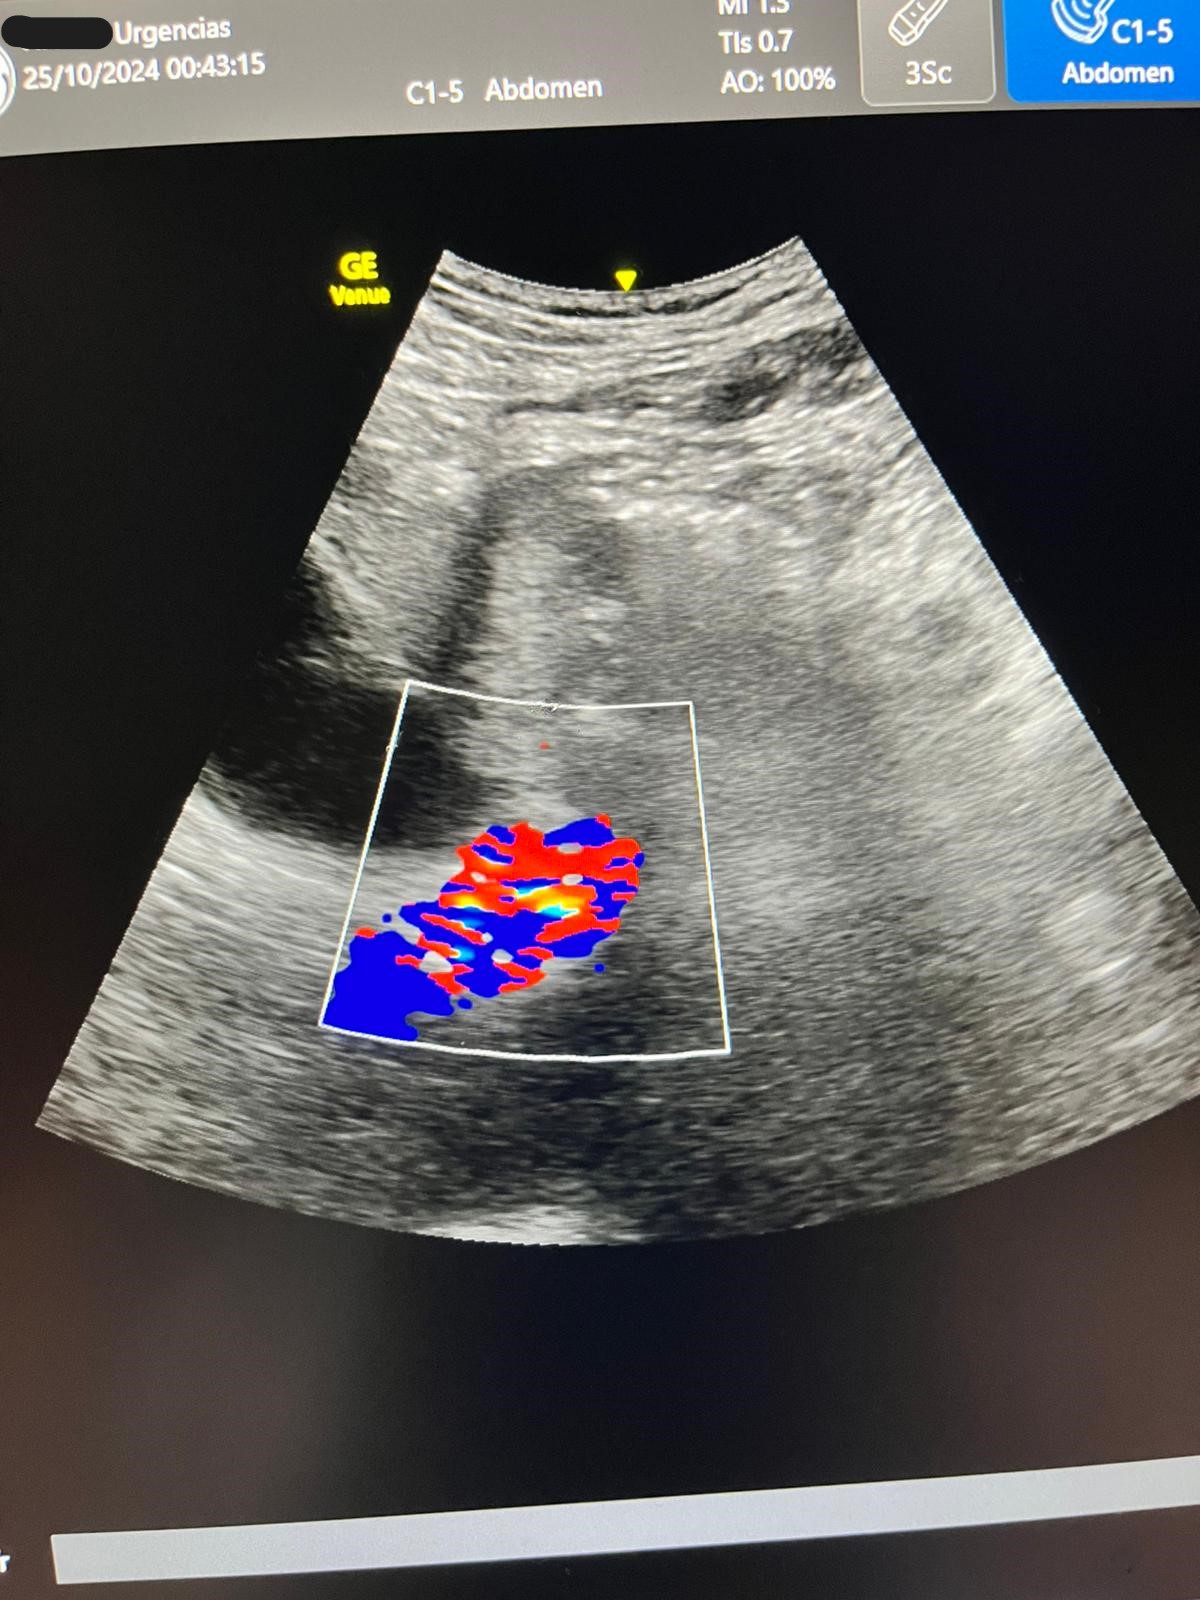

Ecografía: hígado y vías biliares normales sin formaciones expansivas. Coledoco de calibre normal.

Vesícula biliar distendida con litiasis múltiple suncentimétricas y barro biliar de paredes finas.

Páncreas y bazo sin alteraciones Riñones normales, sin dilatación de sistema excretor, urolitiasis ni lesiones expansivas sólidas. Quistes corticales simples en ambos riñones en tercio medio del izquierdo quiste complejo con tabiques finos y calcificación.